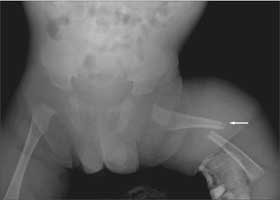

A plain radiograph demonstrated an acute displaced fracture of the left femur (Figure 1). Child Protective Services (CPS) was notified and a skeletal survey was ordered. Images revealed a healing fracture of the right distal radius; an acute linear, nondisplaced fracture of the right parietal skull; and pleural changes associated with fourth and seventh left rib fractures. Also evident were cupping and fraying of the metaphyses of the long bones and demineralized bone density (Figure 2). Results of an ophthalmological examination were normal. An MRI scan of the brain revealed the skull fracture but otherwise showed normal findings.